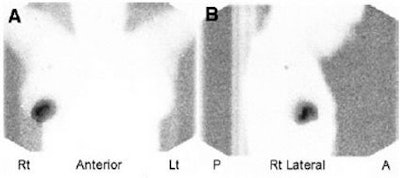

| Sentinel lymph node images acquired on a dual-head gamma camera with 153Gd line-source transmission. On the right is the anterior view; on the left the posterior view. Images courtesy of Elizabeth Clarke and the Journal of Nuclear Medicine |

"A 153Gd line source gives a clear, crisp body-outline image," the authors concluded. "This technique also gives a low radiation dose to the patient and none to the operator. The extra radiation dose to the patient from the 153Gd source is 3 m Sv per (2) views, 1% of the total patient dose from the SLN study." More conveniently, this method can be performed on most dual-head gamma cameras with attenuation-correction capability.